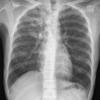

Pneumonia

TB - active

active TB